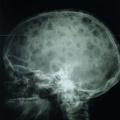

Les plasmocytes myélomateux désorganisent l’homéostasie du stroma médullaire, en activant les ostéoclastes et en inhibant les ostéoblastes. Ce déséquilibre entre résorption et fabrication osseuse conduit à l’apparition de lésions ostéolytiques. Elles sont classiquement « à l’emporte-pièce », principalement dans les os riches en moelle : crâne (fig. 4), rachis, côtes, bassin et os longs (en-deçà des coudes et des genoux, les lésions sont très rares).